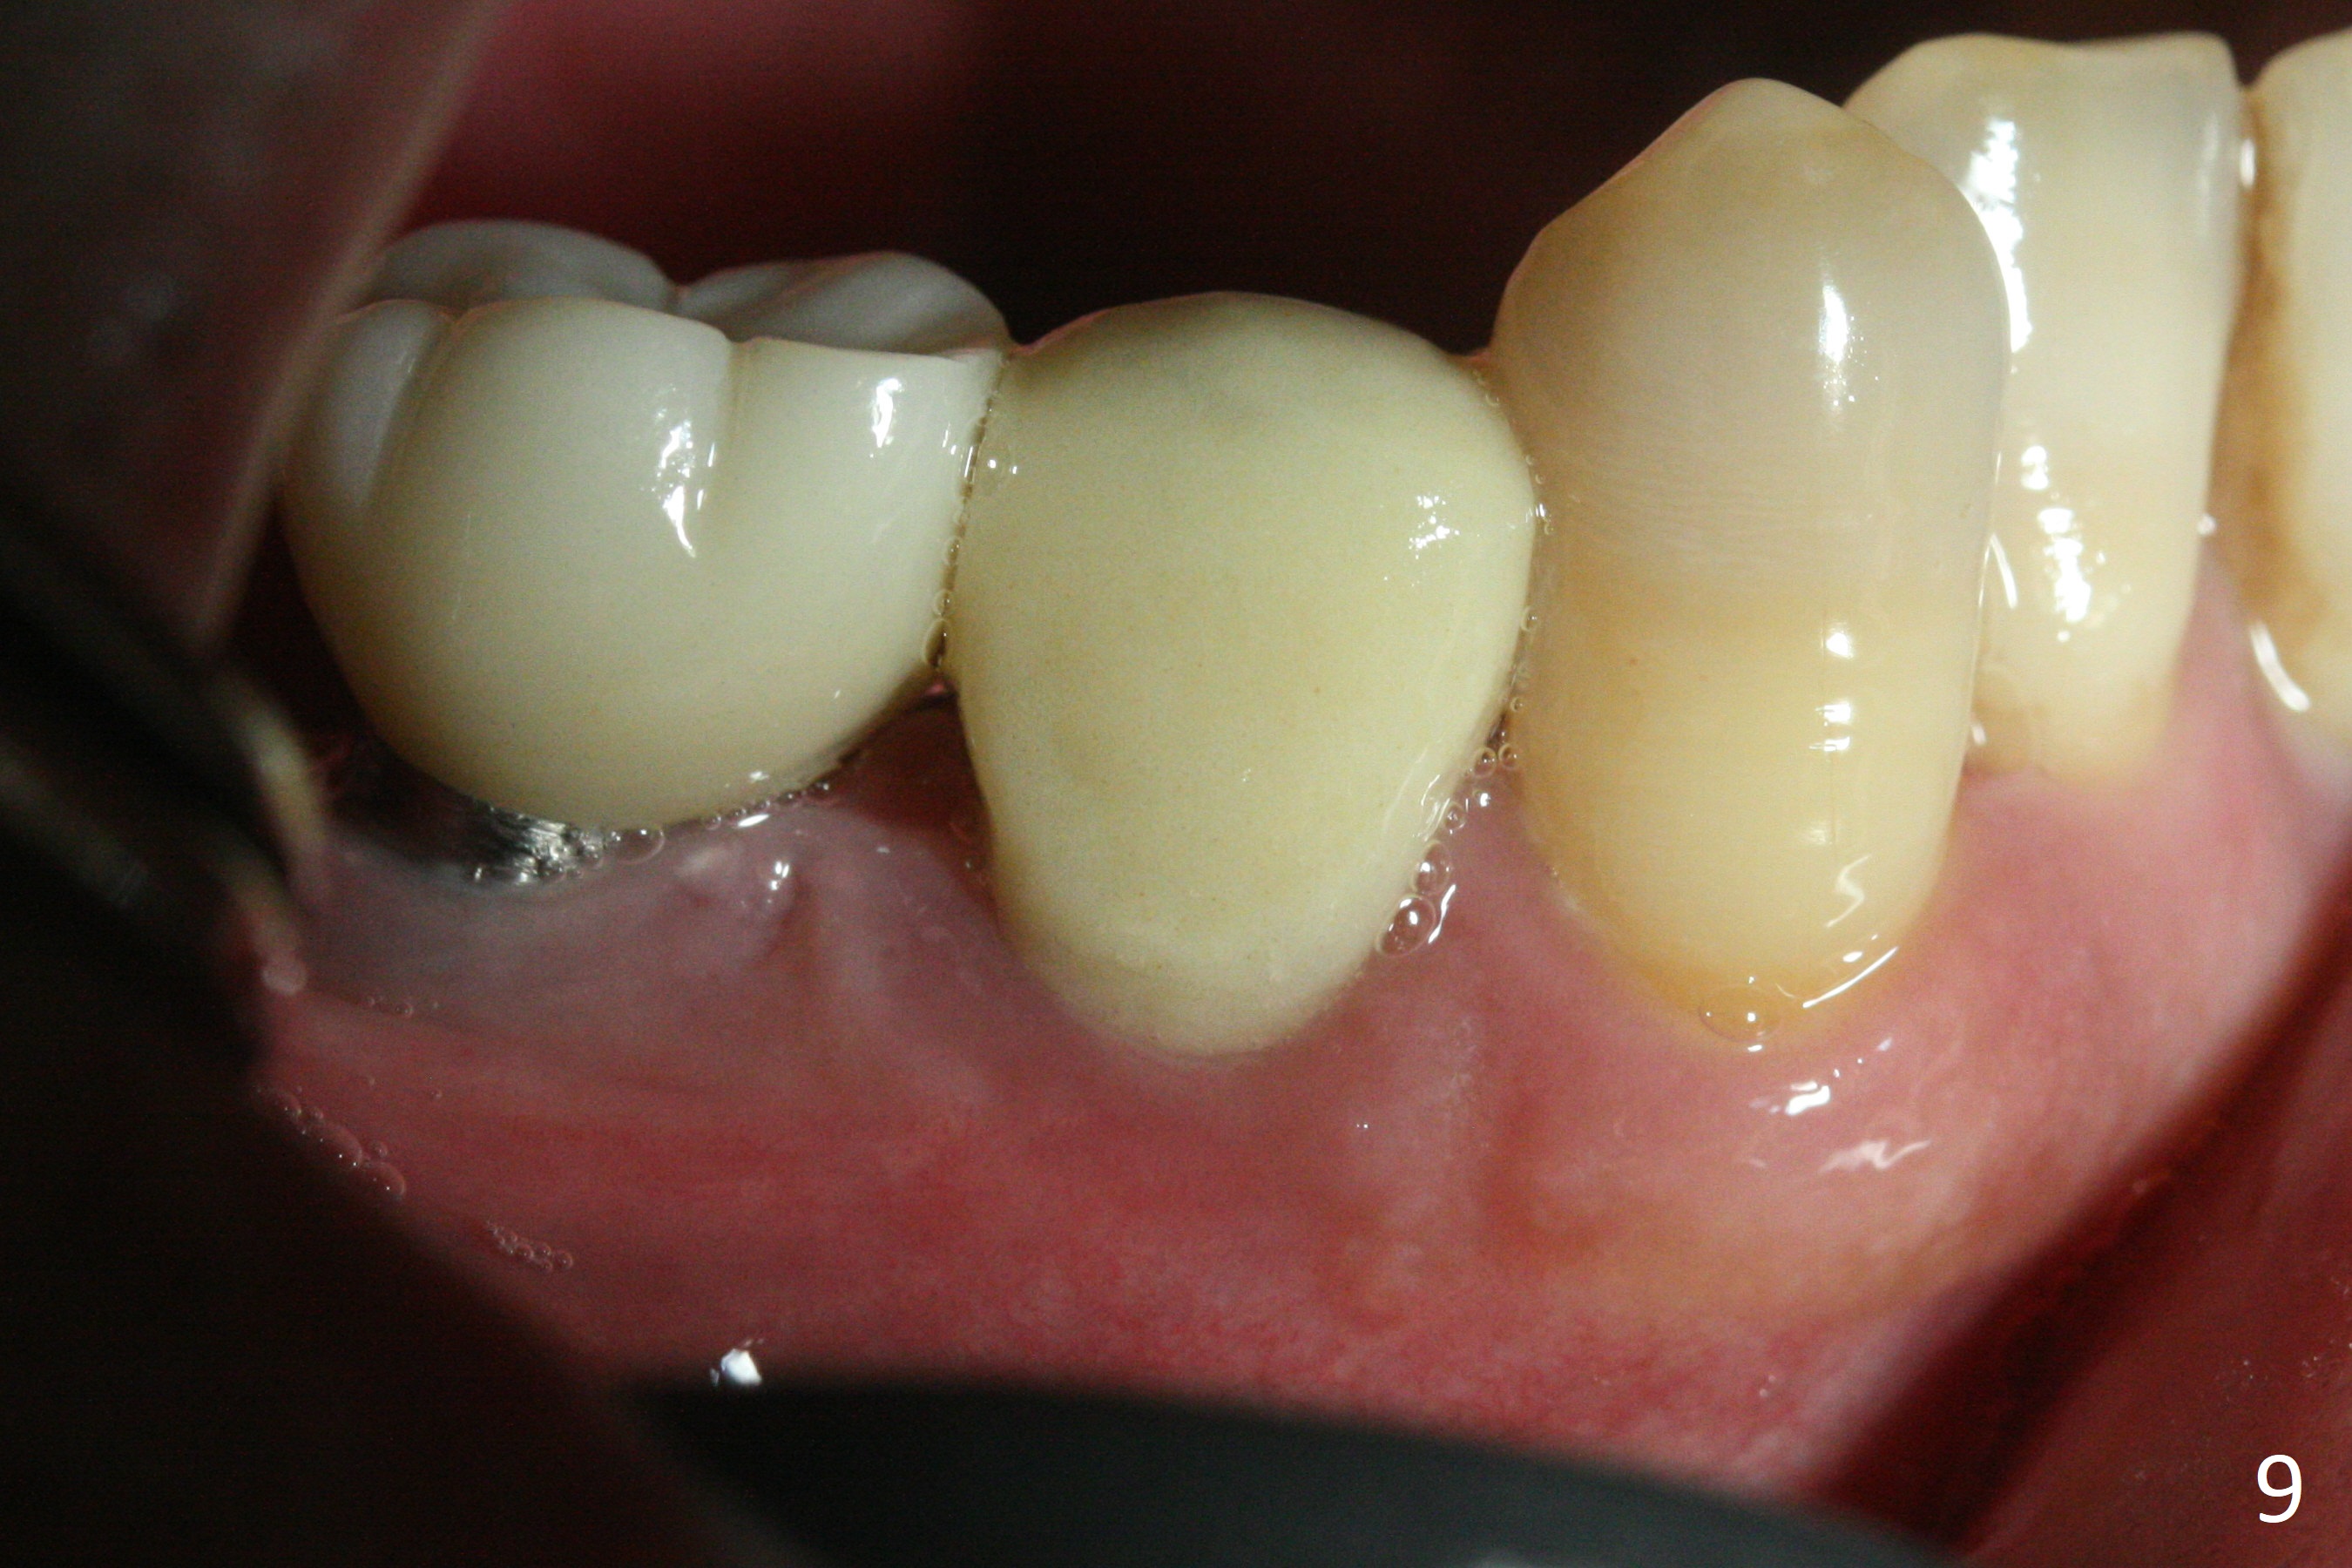

The affected tooth (#28) has buccal gingival recession (Fig.1). As expected, the buccal plate is found low after extraction. Osteotomy is established in the lingual slope of the socket with 1.5 mm drill for 13 mm (Fig.2,3). Following use of Magic Drill 3.3 mm for 13 mm, a 4x11 mm dummy implant is incompletely seated (Fig.4); it is also close to the Mental Loop (Fig.4 red line). After use of Final Drill, a 4x9 mm IBS implant is placed 4 mm and 2 mm subgingival buccal and lingual, respectively (Fig.5) with a large buccal gap (Fig.6 (40 Ncm)). After placement of allograft in the peri-implant space (Fig.7 *), a 4.5x5.7(4) mm abutment is placed (A). A piece of gauze is placed in the remaining buccal space prior to provisional fabrication (Fig.8 *). The space occupied by the gauze is later filled with collagen plug before provisional seating. The gingiva is healthy around the provisional 12 days postop (Fig.9). To reduce buccal gingival recession, the buccal margin of the provisional is shortened 4.5 months postop (Fig.10 arrow). PA taken 5.5 months postop is shown with the implant at 31. The lingual gingiva is erythematous, edematous, and recessive with +BOP and deep pockets 14 months postop (Fig.11). It appears that the small and short implant is not favorable for healing. The infected implant is removed with the missing buccal plate; bone graft is placed 15 months postop (7 months post cementation, Fig.12,13).